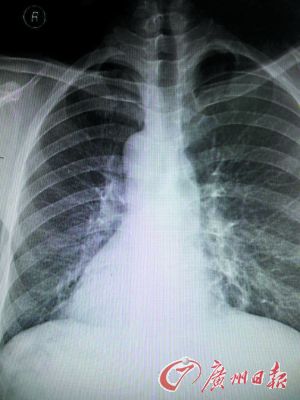

X光片上袁先生的心臟陰影在右邊。

X光片上患者的心臟陰影在右邊。

東莞現(xiàn)鏡面人,五臟六腑長的位置和一般人相反,正常人的心臟、脾臟在左側(cè),肝臟在右側(cè)。但日前,東莞市第八人民醫(yī)院收治的一名病人正好相反,他的心臟、脾臟在右邊,肝臟在左邊。

醫(yī)生趕快拿起聽診器聽診心音區(qū),發(fā)現(xiàn)患者右側(cè)心音較左側(cè)明顯,跟常人相反。經(jīng)胸片、心電圖及B超等檢查后,確診患者為急性化膿性闌尾炎內(nèi)臟反位,也就是“鏡面人”得了闌尾炎。